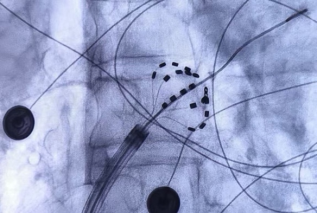

11月11日,我院院长助理、首都医科大学附属北京安贞医院安徽医院副院长、我院心血管内科学科带头人喻荣辉教授团队顺利完成安徽省首例FARAPULSE房颤脉冲消融(Pulsed Field Ablation, PFA)术。

PFA术是国内领先技术,通过施加高频电场脉冲使心肌细胞膜电穿孔,导致细胞程序性死亡,从而达到消除及阻止异常电位传递的目的。因不同组织细胞的电穿孔场强阈值不同,通过调节参数,脉冲电场消融可以实现心肌特异性消融,较为精确地消融靶向心肌组织,而不损伤毗邻组织。PFA的安全性有效性已获验证,优点在于能极大的缩短手术时间,减少传统导管消融并发症。喻荣辉教授介绍:FARAPULSE脉冲消融术的安全性和有效性已获循证医学支持,心脏穿孔等主要并发症显著减少,手术过程更加安全,治疗效果稳定。同时,术中消融过程左房操作平均时间约14分钟,手术时间显著缩短。